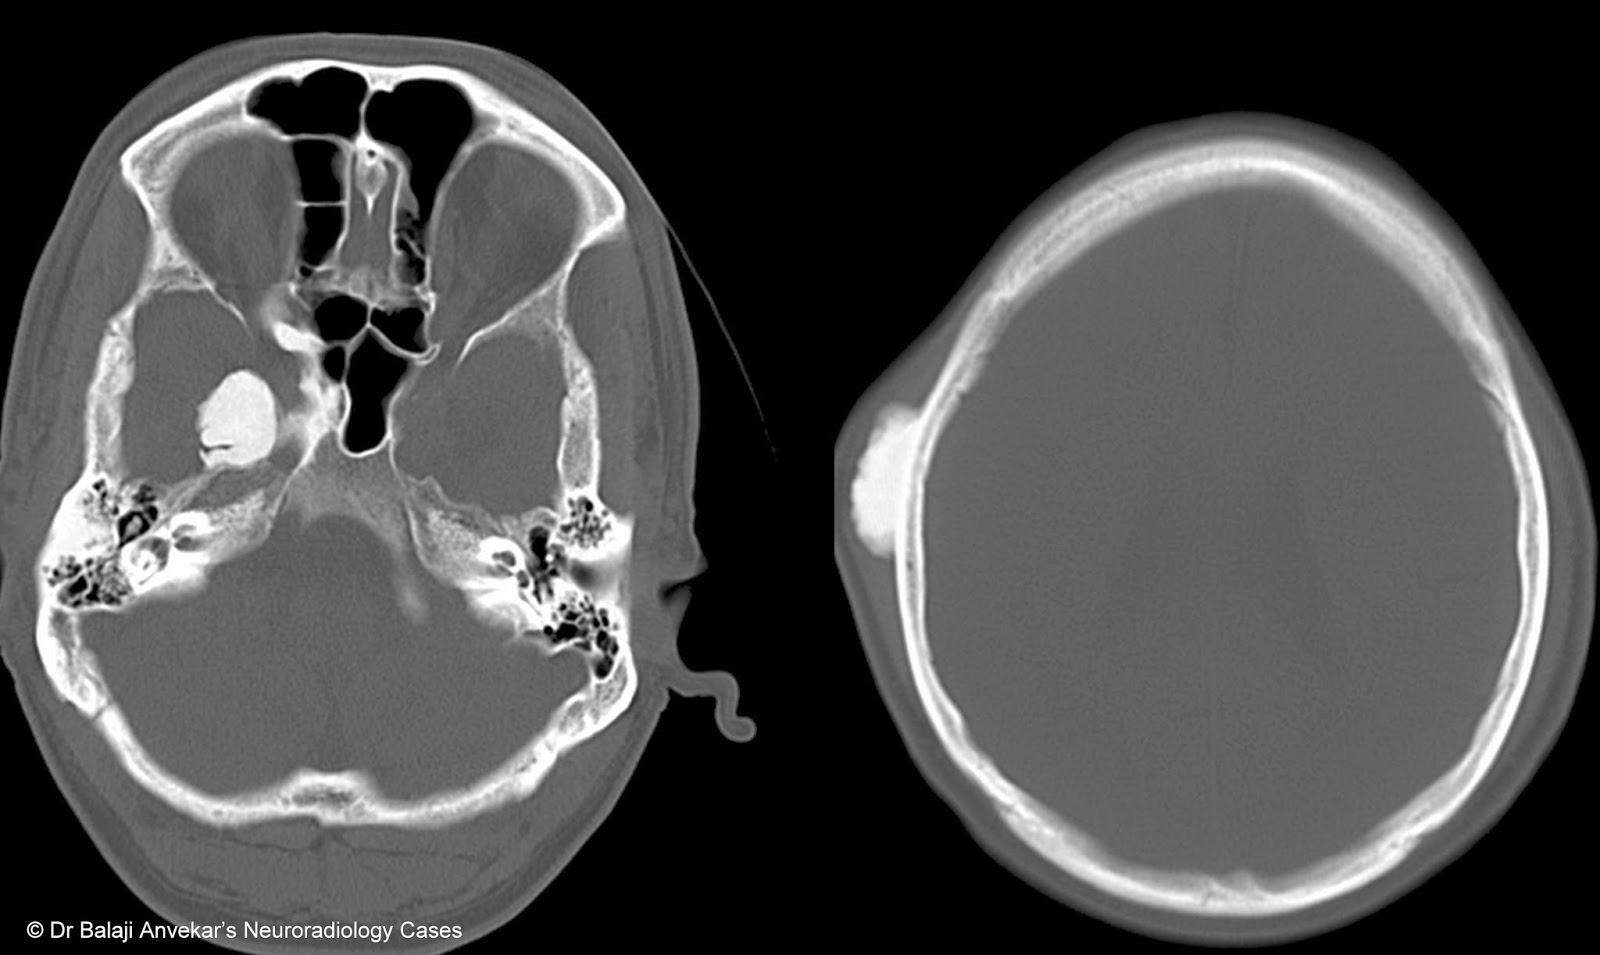

From www.neuroradiologycases.com

Dr Balaji Anvekar FRCR Paranasal sinus osteoma CT Maxillary Osteoma Radiology In patients with multiple osteomas, gardner's syndrome (gs) as an underlying disease needs to be excluded. A bone window algorithm better delineates the details of a bony lesion. This is a patient who had been having brain mri for the past 1,5 yrs for frontal headaches. In this report, we present the case. They have a characteristic lucent nidus <1.5. Maxillary Osteoma Radiology.